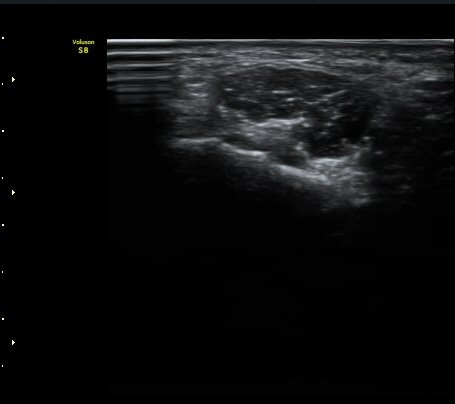

ŽÃËÀÚ¸¦ Á» ´õ ³»ÃøÀ¸·Î °æ»ç¸¦ ÁÖ¾î °¥°í¸®»À °í¸®ÀÇ Ãø¸éºÎ¸¦ °üÂûÇÏ´Ï °¥°í¸®»À °í¸®ÀÇ

ÇÇÁú°ñ ¿¬°á¼º ¼Ò½Ç(°ñÀý)°ú ±¹¼ÒÀû Àú¿¡ÄÚ ºÎÁ¾ÀÌ °üÂûµÇ°í Àú¿¡ÄÚ ºÎÁ¾ ¿ÜÃø¿¡¼­ ö°ñ½Å°æ

½ÉºÎ°¡Áö°¡ °üÂûµÈ´Ù(±×¸² 2, 3, 4,).